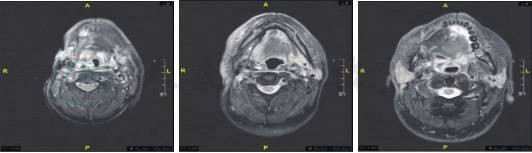

2018-12-11颌面部增强CT提示:术区、右侧颈鞘区、颌下、口咽占位(肿瘤复发),右腮腺下极、咽后、左侧颈上转移淋巴结可能(图1)。

图1 术区、右侧颈鞘区、颌下、口咽占位(肿瘤复发),右腮腺下极、咽后、左侧颈上转移淋巴结可能(皮瓣后缘及下方、右颌下、颈鞘区、右侧口咽壁见软组织肿块,增强后边缘强化,右侧颈内动脉基本受包绕,右腮腺下极、咽后、左侧颈上见环形强化淋巴结影)